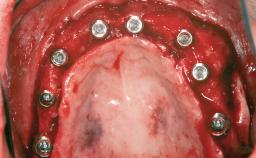

# of Implants 14

A 47-year-old woman who had suffered from aggressive periodontitis requiring a number of periodontal interventions over more than 10 years was referred by her general dental practitioner and periodontologist for bone augmentation and implant therapy. Her failing dentition had already been scheduled for extraction. The patient expressed a desire for implant-supported fixed restorations and esthetic improvement of her lower face. She had agreed to consult with a maxillofacial surgeon after the referring dentist had suggested bone augmentation. An initial examination by the maxillofacial surgeon revealed mobility of all residual teeth in a patient who was very unhappy with the function of her removable partial dentures. Due to periodontally migrated flaring teeth and loss of occlusal support, the vertical dimension of occlusion was dramatically reduced. The patient was displeased with her lower face because of deepened nasolabial, commissural, and supramental folds.

Bone Augmentation Horizontal|Sinus Floor Elevation|Staged|Vertical